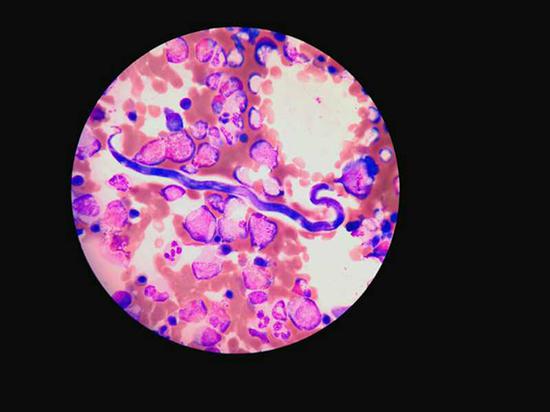

多见于非洲中西部地区的“罗阿丝虫”在显微镜下的形态。 本文图均为 瑞金医院 供图

在检验科主任王剑飙的技术支持下,终于在李艾的骨髓涂片中发现了数量极少的寄生虫微丝蚴。经咨询上海市寄生虫研究所后,断定其为“罗阿微丝蚴”,至此,李艾才被确诊为“罗阿丝虫病”,这在国内是非常罕见的。

专家透露,这是一种多见于非洲中西部的寄生虫,其幼虫为“罗阿微丝蚴”,主要流行于西非、中非多雨林森林及其边缘地带。